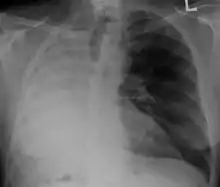

صورة أشعة تُظِهر الرئة اليُسرى مُستأصلة